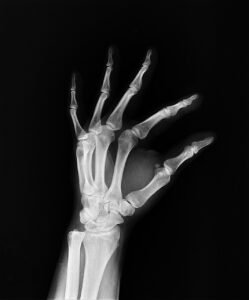

ACL断裂は、前十字靭帯が完全に切れてしまう状態を指します。この靭帯は、膝関節の安定性を保つ重要な役割を果たしており、特にサッカーなどのスポーツでは、その機能が非常に重要です。

ACL断裂の主な原因は、急な方向転換や不適切な着地、過度なストレッチなどです。サッカーでは、ドリブルやシュート、ディフェンスの動作の際にこれらの動きが頻繁に行われるため、選手は特に注意が必要です。